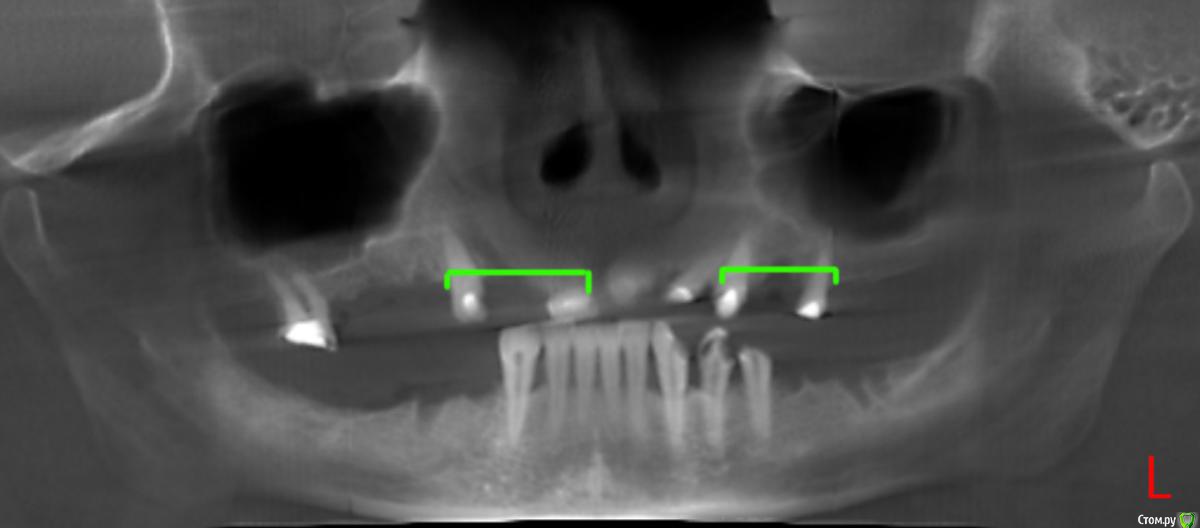

Ксени_Я Опубликовано 27 июня, 2015 Автор Поделиться Опубликовано 27 июня, 2015 (изменено) Bier и Alejandro, спасибо за ответы.Внесу ясность. Я начала лечить зубы. На верхней и нижней челюсти были удалены "плохие" зубы. Во всех верхних были пролечены каналы и установлены временные пломбы. Про низ доктор сказала, что зубы здоровые, там только пару пломб и две коронки. Хотя нижние зубы мне не нравятся, они неровные, в одном из них опущена десна и он немного пошатывается. Повторяю, доктор их исправить отказывается. Т.к. она не устанавливает импланы и на начало лечения я не была к ним готова, доктор предложила бюгельные протезы и объяснила, что если я захочу импланты, в любой момент ними можно заменить протезы. Т.е. вы понимаете, что план лечения есть. На данный момент доктор болеет и я имею то, что вы видите на снимке. ------------------------------------------------------------------------------------------------------------------------------------------- Пока доктор болеет, я поехала на консультацию к доктору, который устанавливает импланты и сделала КТ. Завтра иду на консультацию. Но поскольку я была у него до КТ, по нижним, он сказал что можно установить на передние (восемь штук) сплошные коронки. 1. Соответственно вытекает вопрос делать сплошные или раздельные? 2. И естественно сколько импантов на нижнюю челюсть? Это что касается НИЗА. ВЕРХ. Поскольку там под коронки уже подготовлено меня интересует, как правильно устанавливать их. Насколько я понимаю:3. Там где нет по одному зубу мост на три зуба? Схематически на снимке обвела куда мост на три зуба, а остальные починочные. Так?4. А также интересует, сколько нужно имплантов на верхней челюсти? Всего четыре вопроса, если можно так же по пунктах на них ответьте)) Изменено 27 июня, 2015 пользователем Ксени_Я Ссылка на комментарий